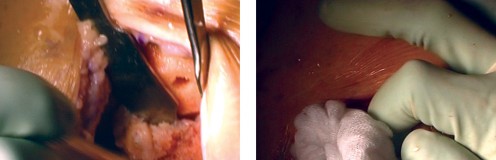

Cementing Technique and Implant Implantation

The hallmark of a cemented TKA is the creation of a durable, interlocking micro-mechanical bond between the host trabecular bone and the polymethylmethacrylate (PMMA) bone cement. PMMA is not an adhesive; it functions as a grout. Therefore, meticulous bone bed preparation is the single most critical factor in preventing aseptic loosening. The resected bony surfaces must be aggressively cleansed using pulsatile lavage to remove marrow, fat, and debris, exposing the porous cancellous bone. Sclerotic areas should be perforated with a small drill bit to enhance cement interdigitation.

The bone must be thoroughly dried immediately prior to cement application. High-viscosity cement is typically mixed under a vacuum to reduce porosity and increase fatigue strength. The cement is applied during its "doughy" phase to both the implant surfaces and the prepared bone. The components are then impacted into place.

Crucially, the cement must be pressurized into the cancellous bone to achieve a penetration depth of 3 to 4 mm. Once the components are seated, all extruded peripheral cement must be meticulously removed with a curette, particularly from the posterior aspect of the condyles and the posterolateral corner, where retained cement fragments can cause severe postoperative pain, third-body wear, or impingement. The knee is then held in full extension with axial compression applied until the exothermic polymerization process is complete and the cement is fully cured.